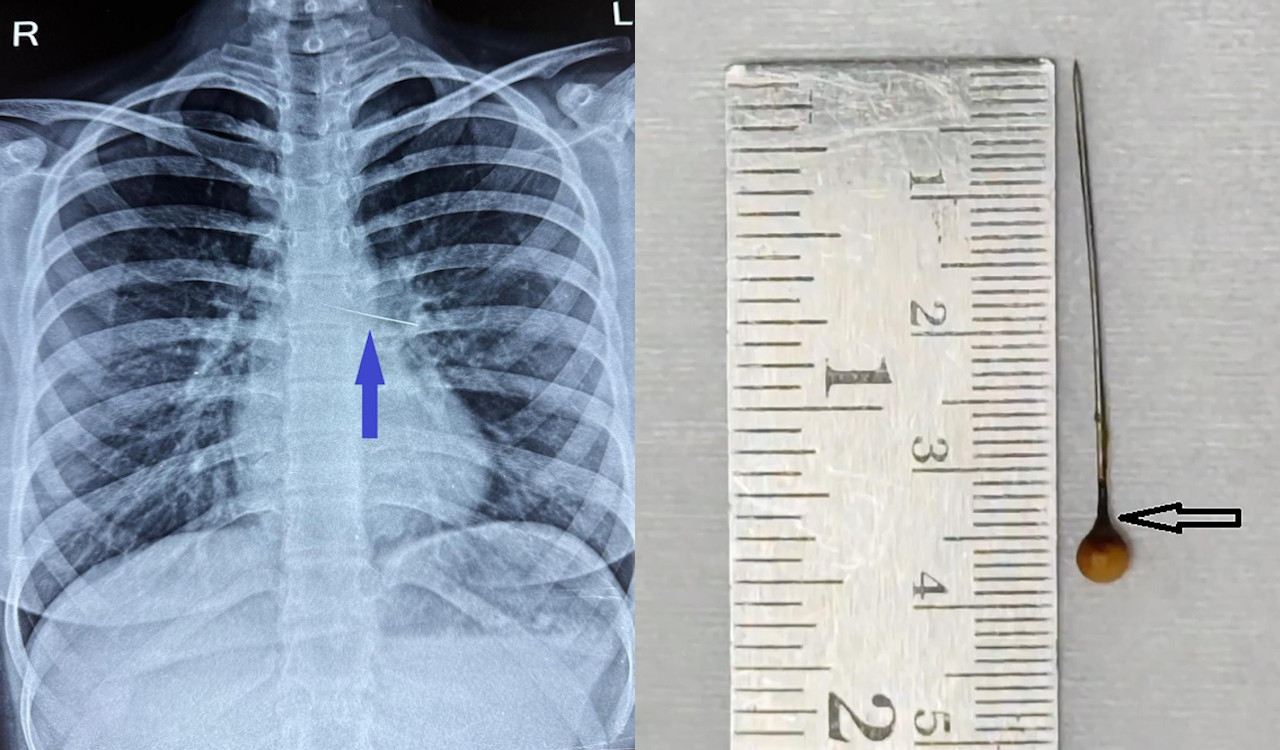

Шпилька на рентгенівському знімку грудної клітини дівчини та після видалення з організму. Bairy et al. / BMJ Case Reports, 2025

Коли дівчина зав’язувала шарф на голові, вона тримала в зубах французьку шпильку, тобто голку з головкою, і зрозуміла, що та опинилася всередині її тіла. Не розуміючи, вона вдихнула чи проковтнула шпильку, дівчина звернулася до лікарні. Там їй провели ендоскопію стравоходу, але в ньому шпильку не знайшли. Після цього пацієнтці зробили рентген, виявивши шпильку в бронхах лівої легені дівчини. При цьому вона не мала жодних симптомів пошкодження легені, маючи нормальну частоту дихання та насичення крові киснем на 97 відсотків, а в її крові не знайшли ознак запалення.